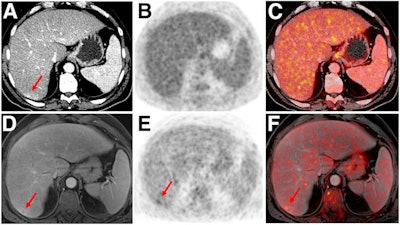

Indeterminate lesion on PET/CT classified by PET/MRI for 53-year-old man with lung cancer. Contrast-enhanced CT (A), PET (B), and fused F-18 FDG PET/CT (C) images are displayed in comparison with contrast-enhanced T1-weighted MRI (D), PET, and fused F-18 FDG PET/MRI (F) images. In CT (A), hyperdense, subcentimeter liver lesion (arrows) in segment VII is suggestive of transient hepatic attenuation difference or small hemangioma. As malignancy cannot be excluded, it needs further investigation. On PET/MRI, lesion is clearly classified as metastasis because of contrast enhancement and tracer uptake due to later acquisition time point. Follow-up CT confirmed diagnosis after 78 days. Image courtesy of SNMMI.The study suggests that PET/MRI could be an effective alternative to PET/CT for tracking and treating cancer patients, according to the authors.